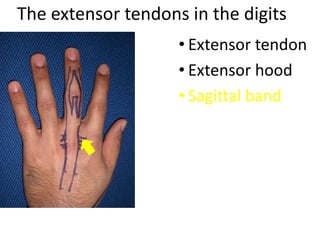

- It describes flexor tendon zones, extensor compartments, and pulley system anatomy.